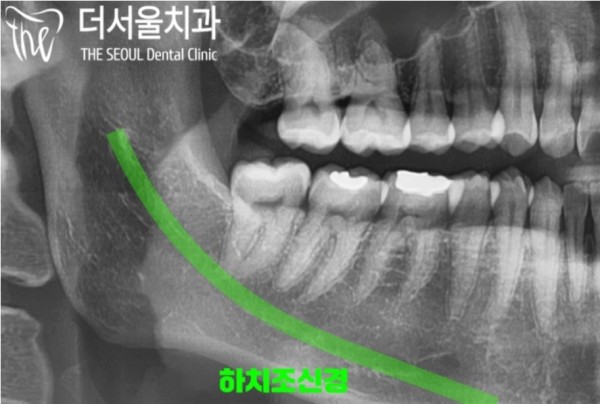

파노라마 엑스레이로 보았을때에는 신경관과

사랑니 뿌리가 아주 가까워 보이는것이 문제인 상황입니다.

저 신경을 잘못건드리면 안면마비, 신경손상... 아주 큰 부작용이 생길 수 있습니다.

Panorama X-ray shows that the neural tube and

The problem is that the wisdom tooth roots look very close.

If you touch those nerves incorrectly, you can have very big side effects, like facial paralysis, nerve damage.